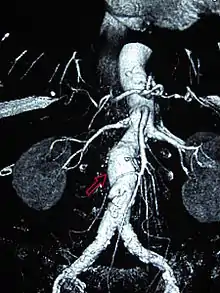

| CT reconstruction image of an abdominal aortic aneurysm (white arrows) | |